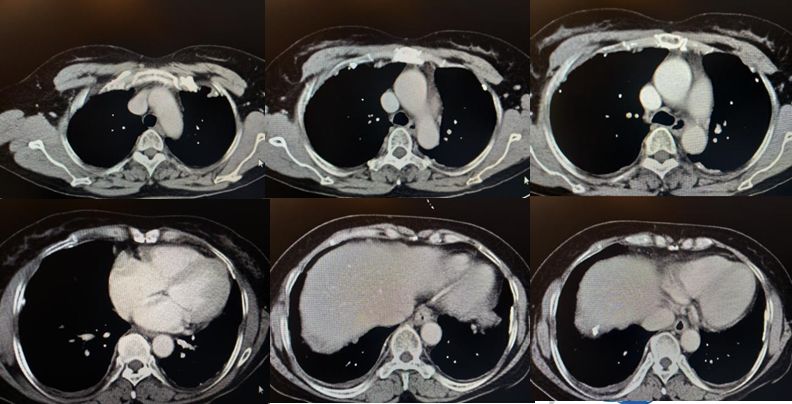

图示:2018-11-27胸部CT影像

•入院后查血肿瘤标志物正常,T-SPOT阴性。胸部CT见两肺内少许絮索条影,两侧胸膜结节状增厚伴散在钙化。